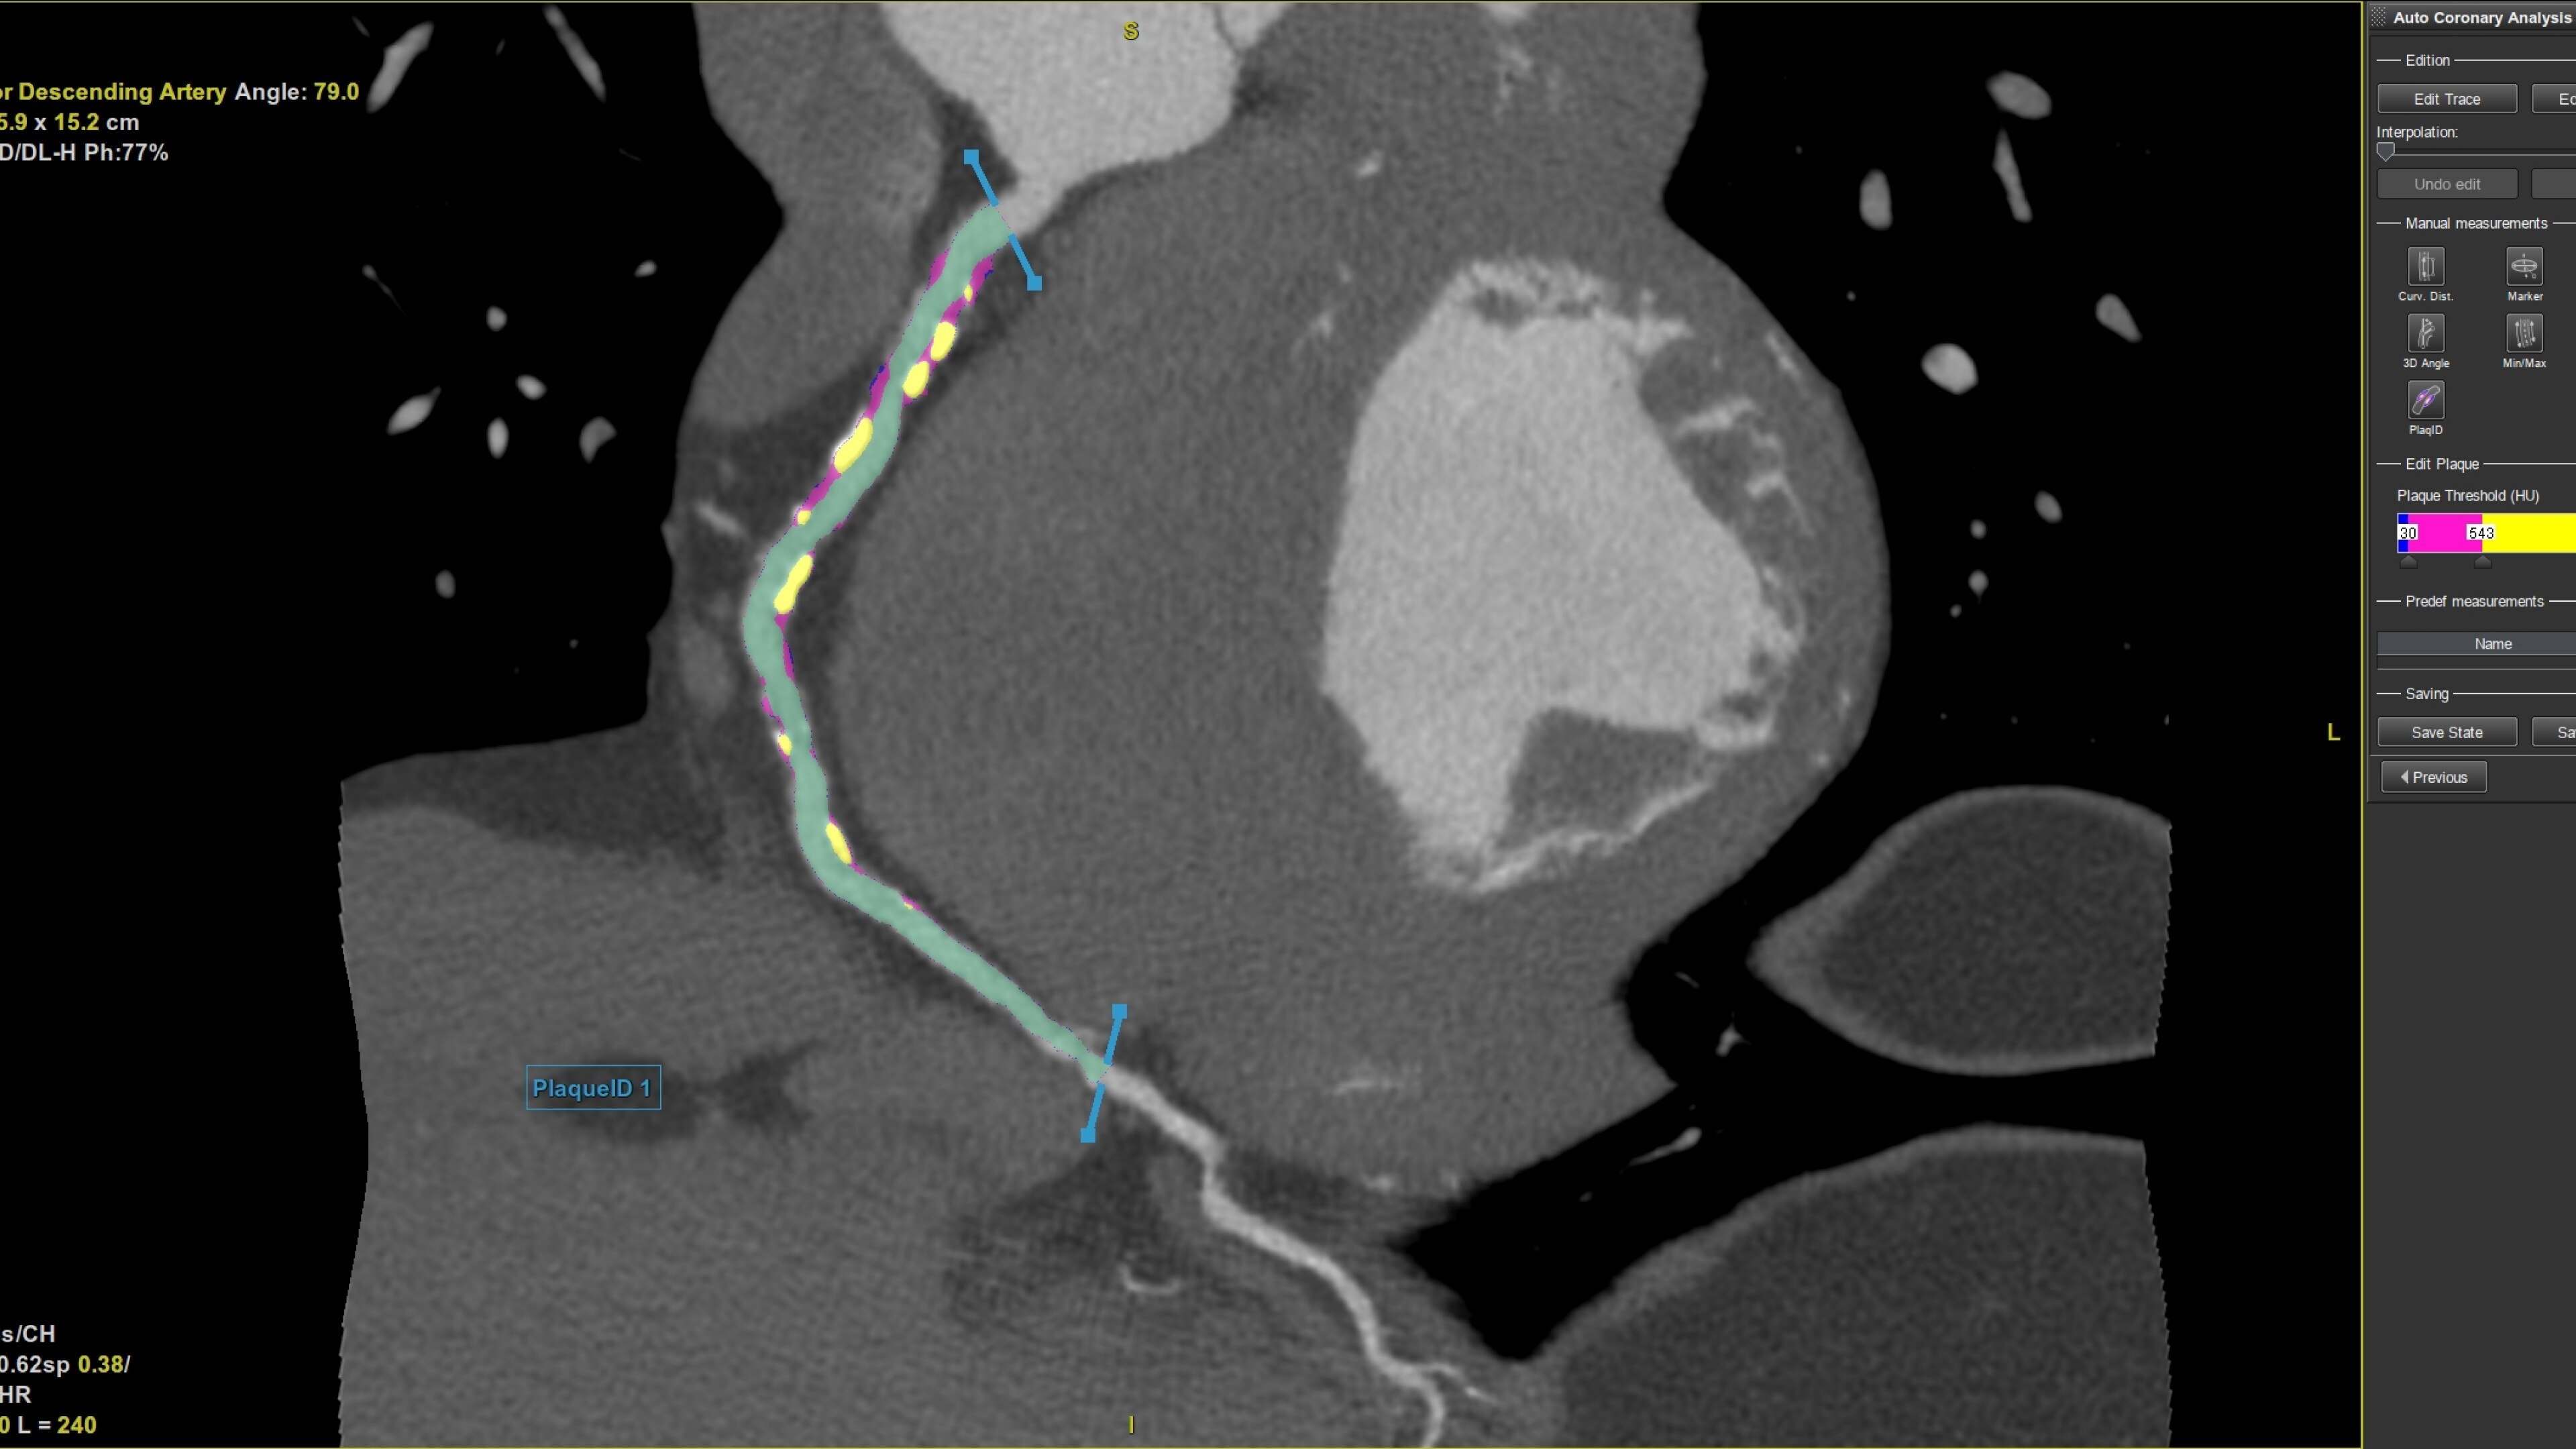

Plaque ID tool assists in visualizing and quantifying plaque burden

• Plaque ID provides volume measurements for four distinct Hounsfield ranges to aid with identification and visualization of coronary plaque